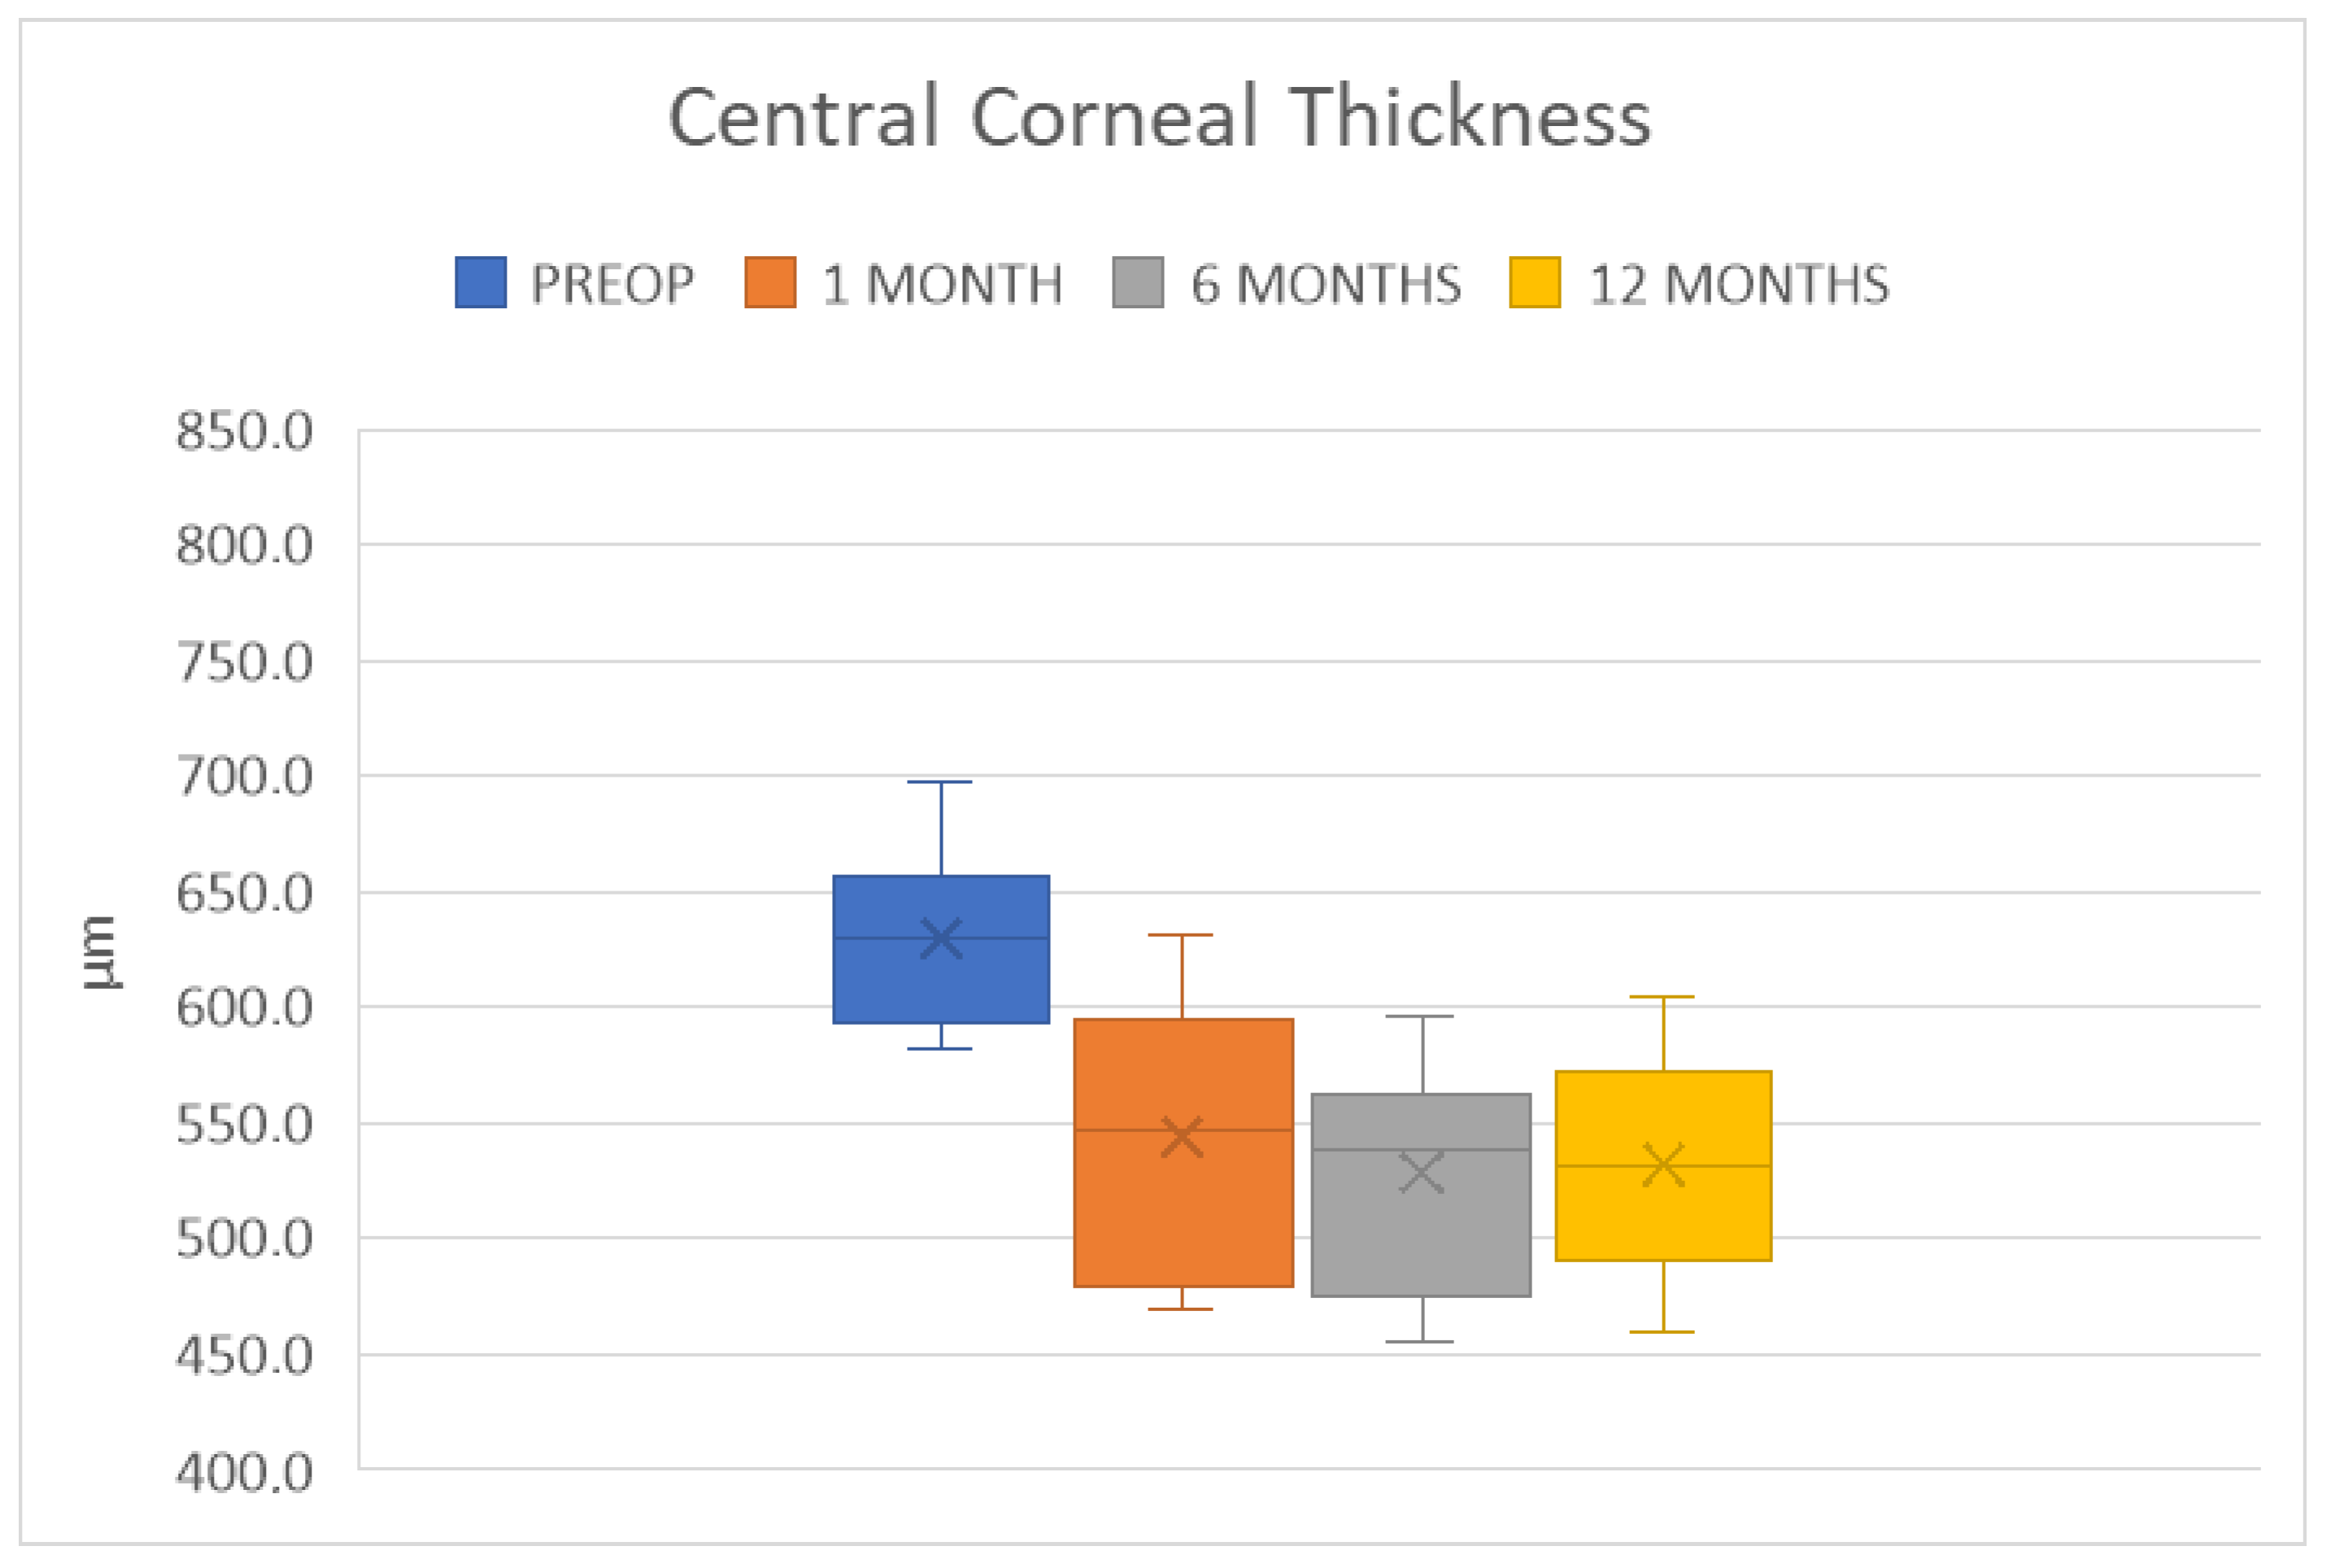

4. Results

| CCT (µm) | 629 ± 39 |

| Parameter Measured | 6 Months | 12 Months | ||

|---|---|---|---|---|

| BCVA (LogMAR) | 0.5 ± 0.3 | p < 0.0001 | 0.3 ± 0.2 | p < 0.0001 |

| CCT (µm) | 528 ± 46 | p < 0.0001 | 532 ± 45 | p = 0.0001 |

| ECD (cells/mm2) | 2181 ± 190 | 1926 ± 199 | ||

| KMIN (D) | 41.7 ± 1.8 | p < 0.001 | 42.0 ± 1.2 | p = 0.001 |

| KMAX (D) | 45.3 ± 1.5 | p < 0.0001 | 45.1 ± 1.2 | p < 0.0001 |

| AVK (D) | 43.5 ± 1.4 | p < 0.0001 | 43.5 ± 1.1 | p < 0.0001 |